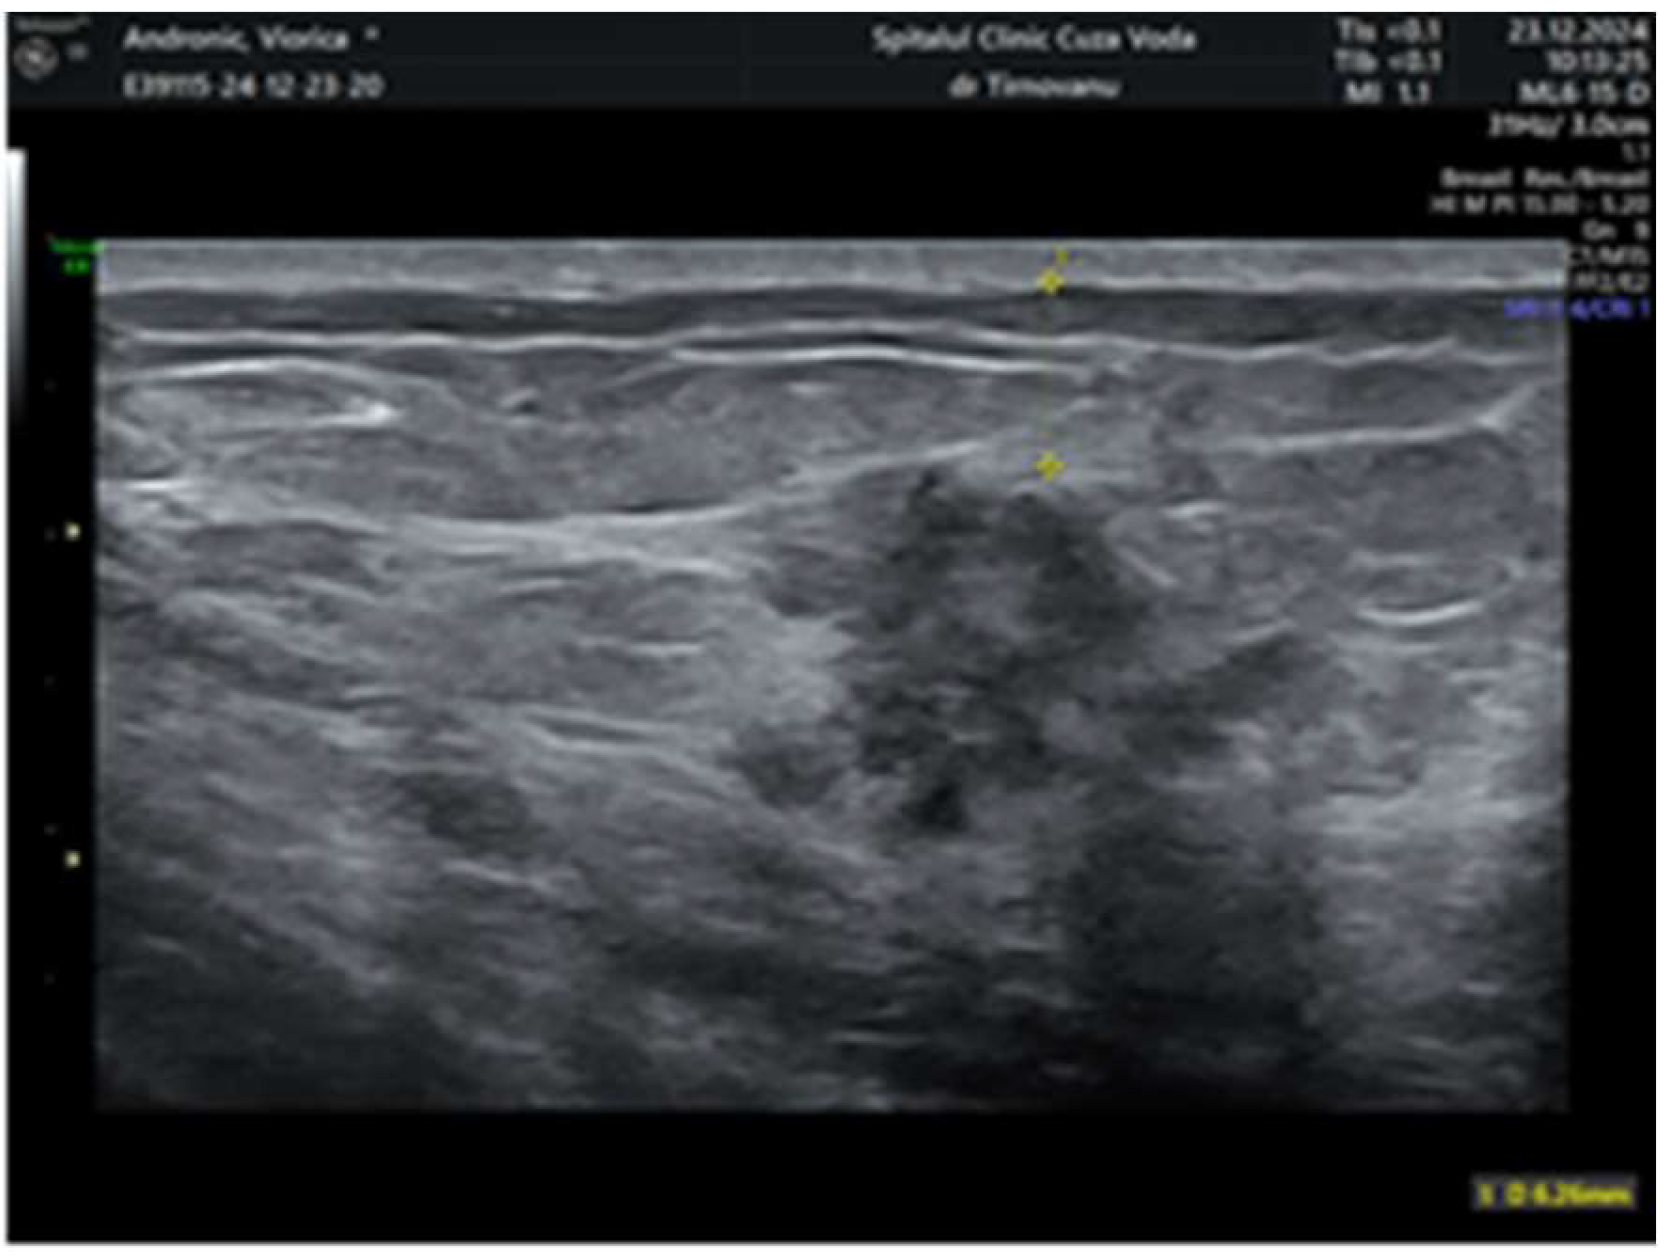

2. Case Report